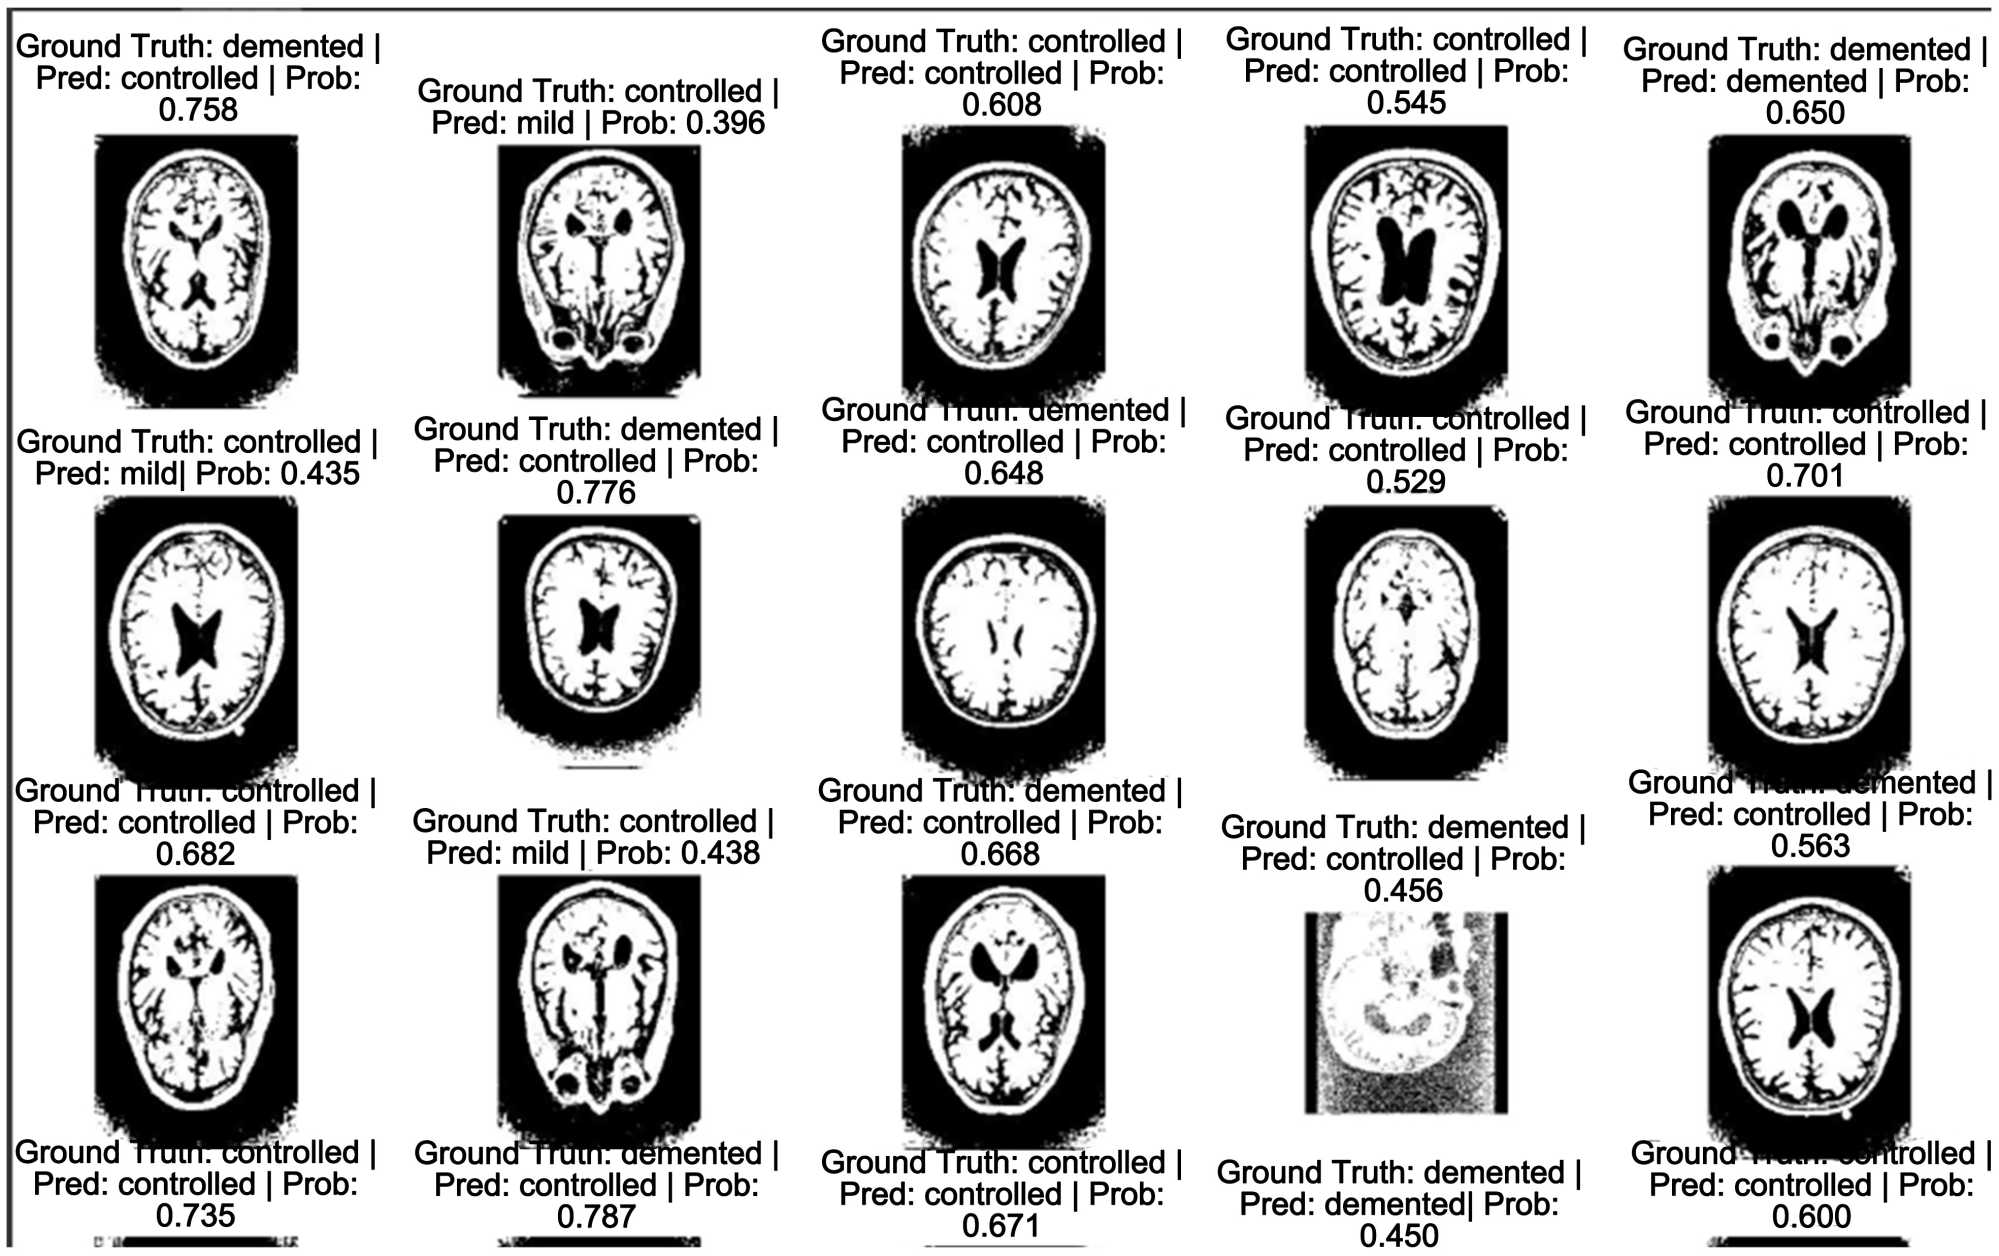

5.4. Evaluation on Testing Set

The testing dataset used was the OASIS-3 dataset underwent the same image segmentation and data augmentation techniques as the Kaggle dataset. The model has an accuracy of 97.34% on the validation dataset and 81.25% on the testing dataset. The fact that the validation dataset achieved a slightly lower accuracy than the testing dataset proves that the model was able to extract some relevant features from the Kaggle dataset and utilize it in the classification on the OASIS-3 dataset. (Figure 16) gives us a representation of how the model performed over the validation set. The image shows that the model was able to predict the correct labels for the different MRI brain scans in the OASIS-3 dataset.

Figure 16. Predictions made on the OASIS-3 dataset.